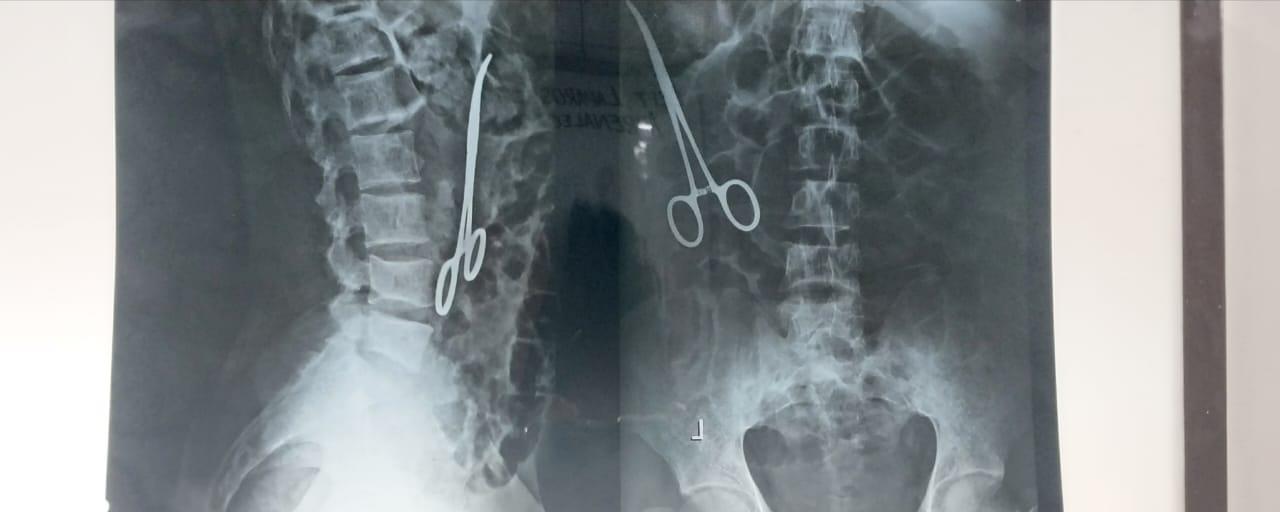

Job’s friends have a Res Ipsa Loquitor view of suffering. Res ipsa loquitor is Latin for “the thing speaks for itself.” This is a lawyer’s argument to prove negligence when traditional evidence may be lacking. For example, if an X-ray reveals a pair of forceps left inside a patient following surgery, the mere presence ofContinue reading “There Are Exceptions to the Principle of Sowing and Reaping. Job 21:13.”